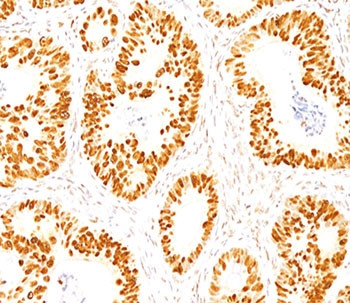

Product information "Anti-p53, clone DO-7"

| Application: | FC, ICC, IF, WB, IHC (paraffin) |